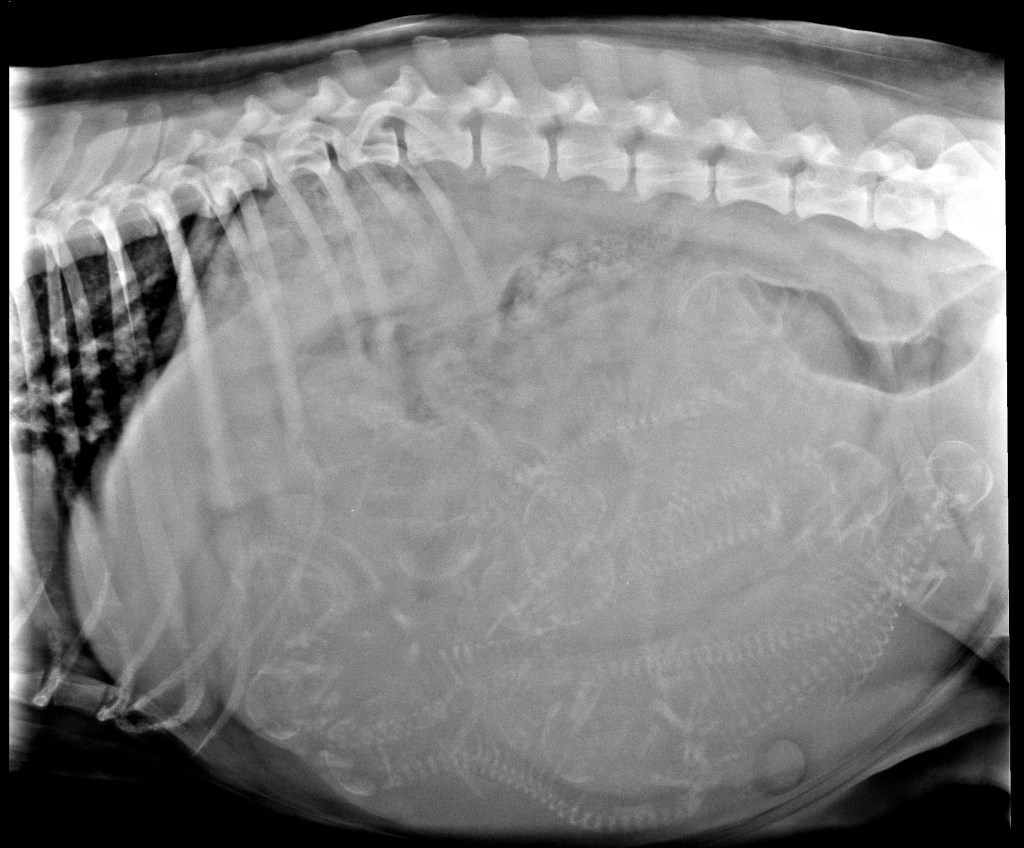

- 16-11-2021, 8 weken drachtig: 33,4kg dag 54 röntgenfoto

Op 16 november maakt Douwe nog een röntgenfoto om te kijken hoeveel pups er werkelijk in zitten. Het is weer heel druk daar binnen en moeilijk te tellen. We komen uit op 9 of 10 pups. De werpkist staat al klaar en dan is het wachten op de eerste signalen dat de bevalling aanstaande is. We temperaturen haar gedurende 10 dagen al meerdere keren per dag. Haar temperatuur schommelt tussen 37,6°C en 38,4°C. Op zondagmorgen 21 november is haar temperatuur opeens 37,3. Ze graaft een gat in een hoek van de tuin en heeft geen zin in haar brokken. Zijn dit de eerste signalen? In de loop van de dag stijgt haar temperatuur weer na normale waarden. Dit gaat zo twee dagen door. Tyske heeft ondertussen een heleboel knuffels op de bank gelegd. Het is wel duidelijk waar ze wil bevallen, op de bank net als de vorige keer. Nu ben ik voorbereid, ik heb de bank geprepareerd voor een bevalling. Als de bevalling zich aankondigt en Joop een van de knuffels op de grond gooit om plaats te maken wordt die steevast door Tyske opgepakt en terug gelegd.